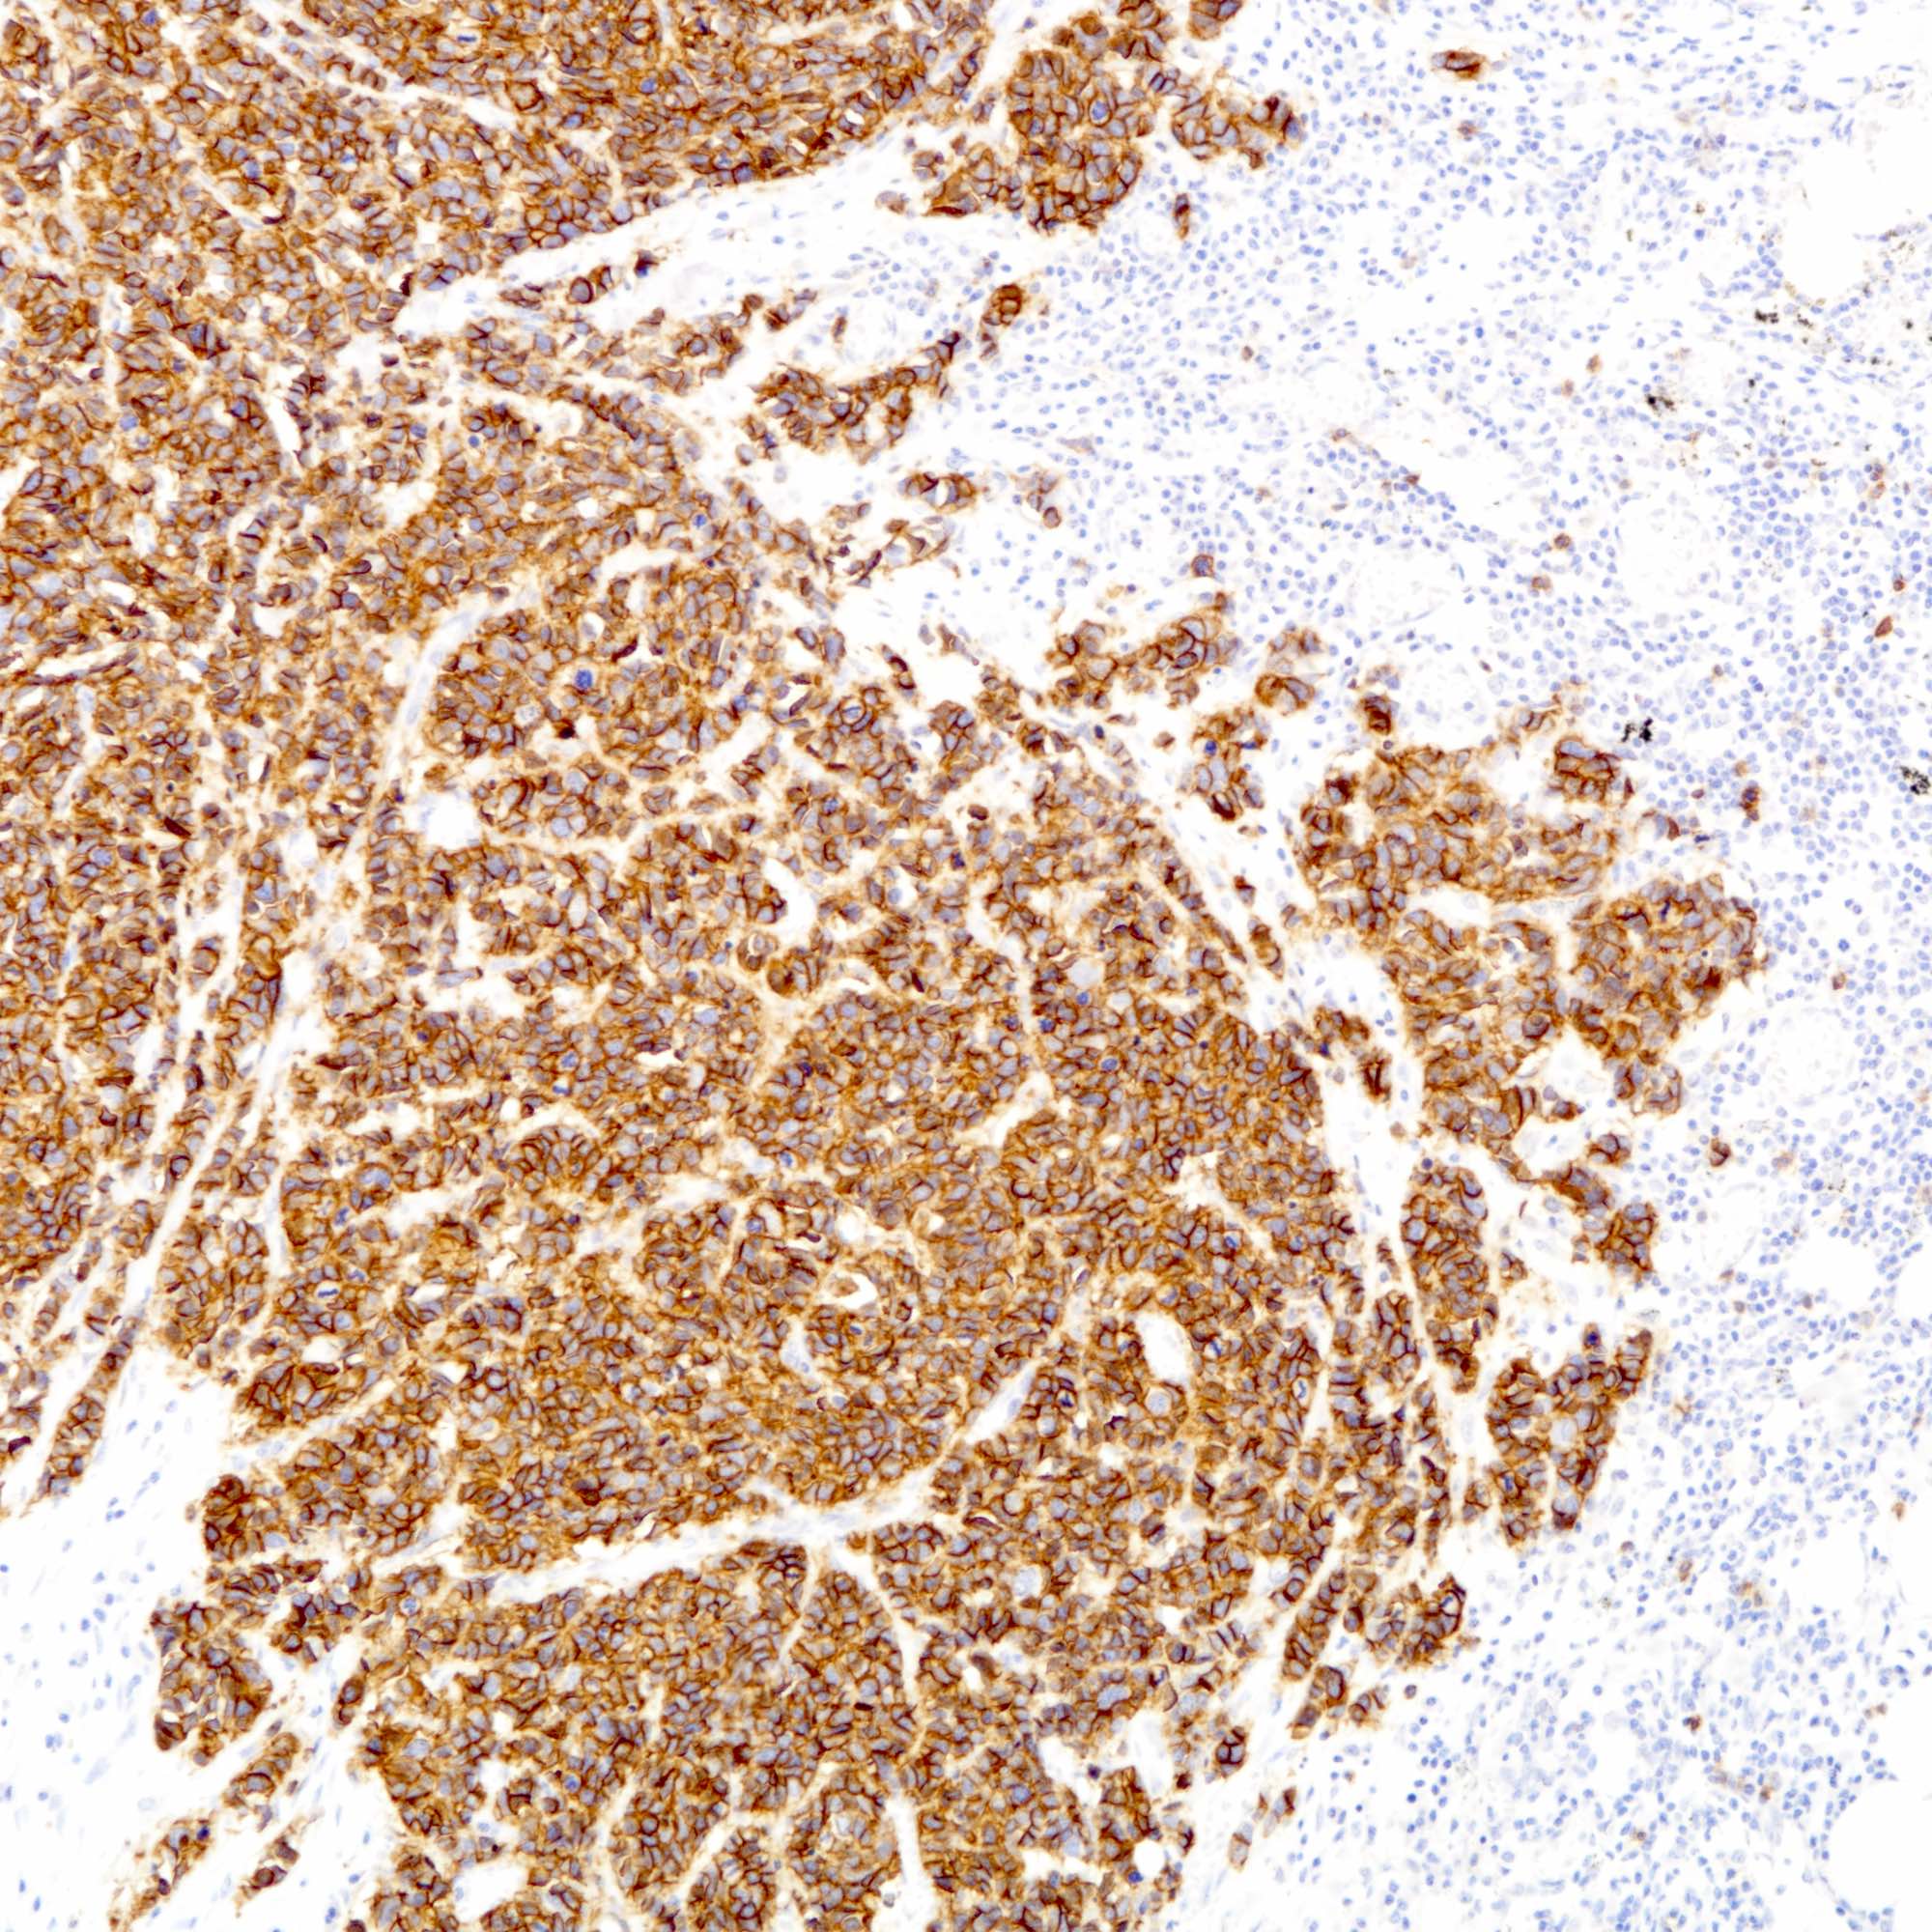

Contributed by Joshua J.X. Li, M.B.Ch.B., Gary M. Tse, M.B.B.S. and Kristen E. Muller D.O.

Small cell carcinoma

Large cell carcinoma

Positive stains

- Cytokeratins:

- Neuroendocrine markers:

- The tumor cells are diffusely positive for synaptophysin and focally positive for chromogranin.

- The tumor cells are diffusely positive for synaptophysin and focally positive for chromogranin.